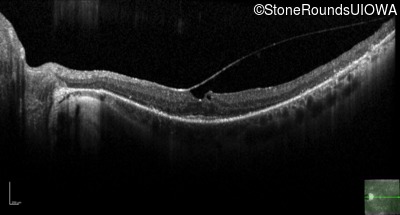

Optical Coherence Tomography - Left - 20/25 sc

Exemplar / OCT Stack

OCT Stack